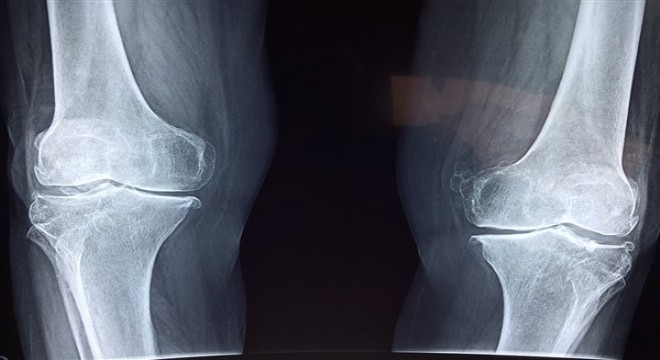

Sigara kullanımı kemik kaynamasını geciktiriyor

Farklı nedenlerden dolayı kırılan kemiklerde kaynamanın gecikmesi veya kaynamanın olmaması, yaş, cinsiyet, beslenme ve yaşam biçimi gibi birçok etkene bağlı olarak gerçekleşiyor.

Farklı nedenlerden dolayı kırılan kemiklerde kaynamanın gecikmesi veya kaynamanın olmaması, yaş, cinsiyet, beslenme ve yaşam biçimi gibi birçok etkene bağlı olarak gerçekleşiyor. Sigara kullanımının kemik kaynamasını geciktirdiğini vurgulayan uzmanlar, beslenme ve şeker hastalığı gibi faktörlerin de kaynamanın gecikmesinde etkili olduğuna dikkat çekiyor. Uzmanlar, kemik sağlığı için D vitamini açısından zengin olan güneş ışınları ile kalsiyum ve protein açısından zengin yiyeceklerden faydalanılmasını öneriyor.